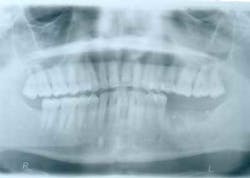

Approximately eight weeks later, a GBR procedure was done utilizing a vestibular incision approach, reflecting the mucoperiosteal flap beyond the ascending ramus. A combination of FDBA (regeneross, Biomet 3i) and autogenous graft particles harvested from the ascending ramus were placed on the deficient ridge after making cortical perforations. The graft materials were covered with a titanium-reinforced dense polytetrafluoroethylene (d-PTFE) membrane (cytoplast, osteogenics) that was tacked into place in order to maintain graft stability during healing. The membrane extended approximately 2 mm beyond the bone graft materials and was placed up the ascending ramus. Immediately after surgery, a panoramic radiograph was taken (Fig. 3).

Fig. 3